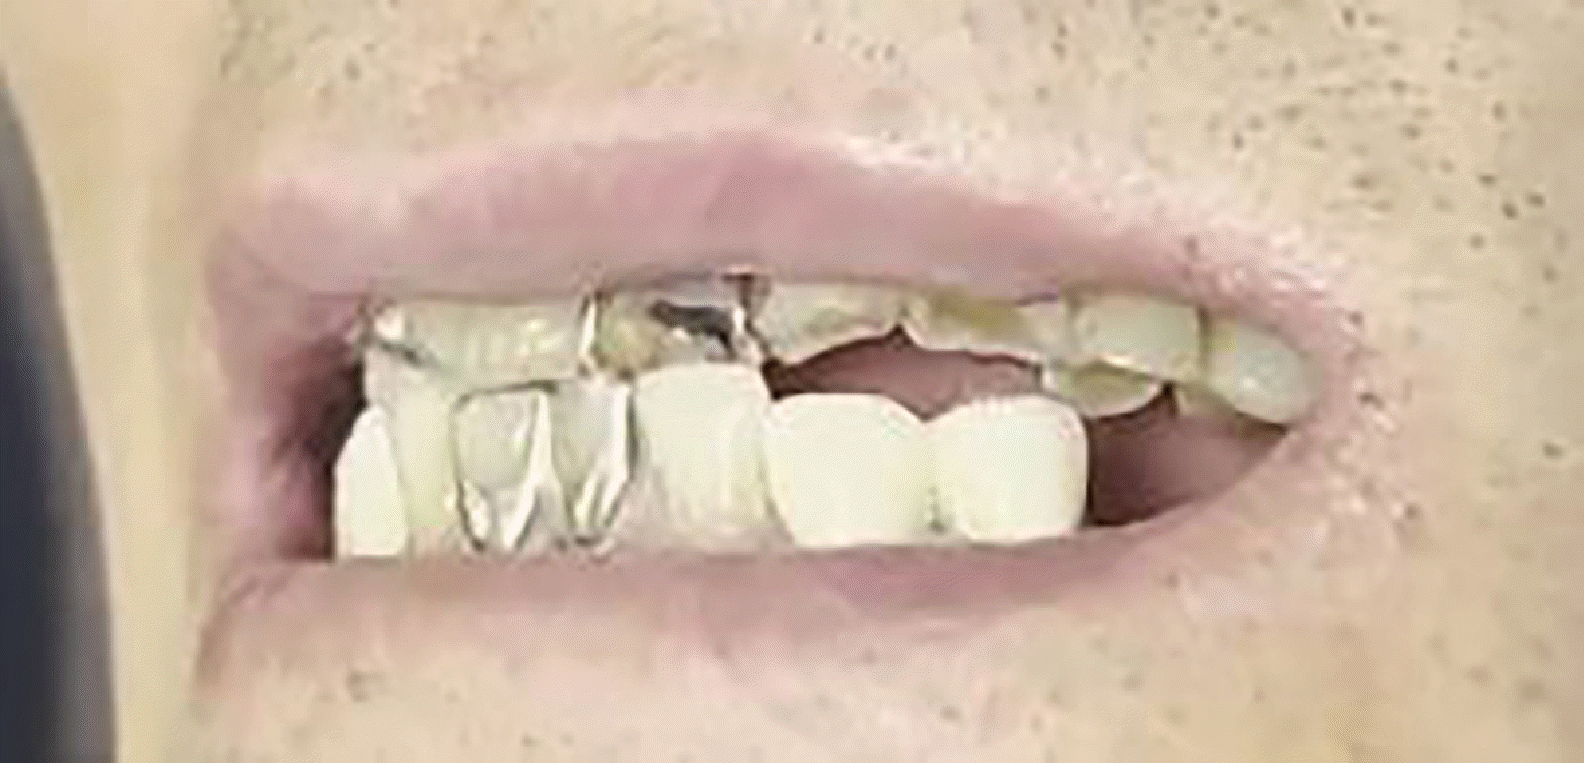

Fig. 1

An image of an edge-to-edge occlusion guided to a centric relation position using chin-point guidance.

At the initial visit, the patient exhibited a skeletal Class III relationship with edge-to-edge incisal contact in CR guided by chin-point technique (Fig. 1). TMJ assessment showed normal mouth opening (> 40 mm) without joint or muscle symptoms, and no signs of popping, crepitus, or pain on loading test (per Dawson).7 Habitually, the mandible closed anterosuperiorly, with the mandibular incisors sliding along the labial surfaces of the maxillary incisors (Fig. 2). Treatment commenced with the mandible guided into CR, achieving stable anterior end-to-end contact at the appropriate vertical dimension.